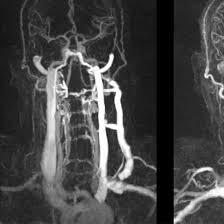

CT Angiography of the neck is a kind of non-invasive imaging technique. It is taken through the blood vessels in the neck, including the carotid and vertebral arteries. A contrast dye is injected into the bloodstream and then a CT scan is used to provide cross-sectional images of the arteries and veins. This scan can detect blockages, aneurysms, narrowing, or abnormalities in the blood vessels. CT angiography of the neck is crucial for diagnosing vascular diseases and planning treatment for patients at risk of stroke or other circulatory disorders.

A contrast dye is injected into a vein, preferably in the arm, to make the blood vessels stand out more during the scan. The patient will lie on a table that is pushed into the CT scanner, where it takes rapid X-rays of the neck. Detailed images from the different cross-sections capture the blood vessels, including carotid and vertebral arteries. With the aid of a computer, images created will be processed to have 3D models of the arteries to view the different findings. A radiologist reviews the images to detect blockages, narrowed segments, or other blood vessel abnormalities.